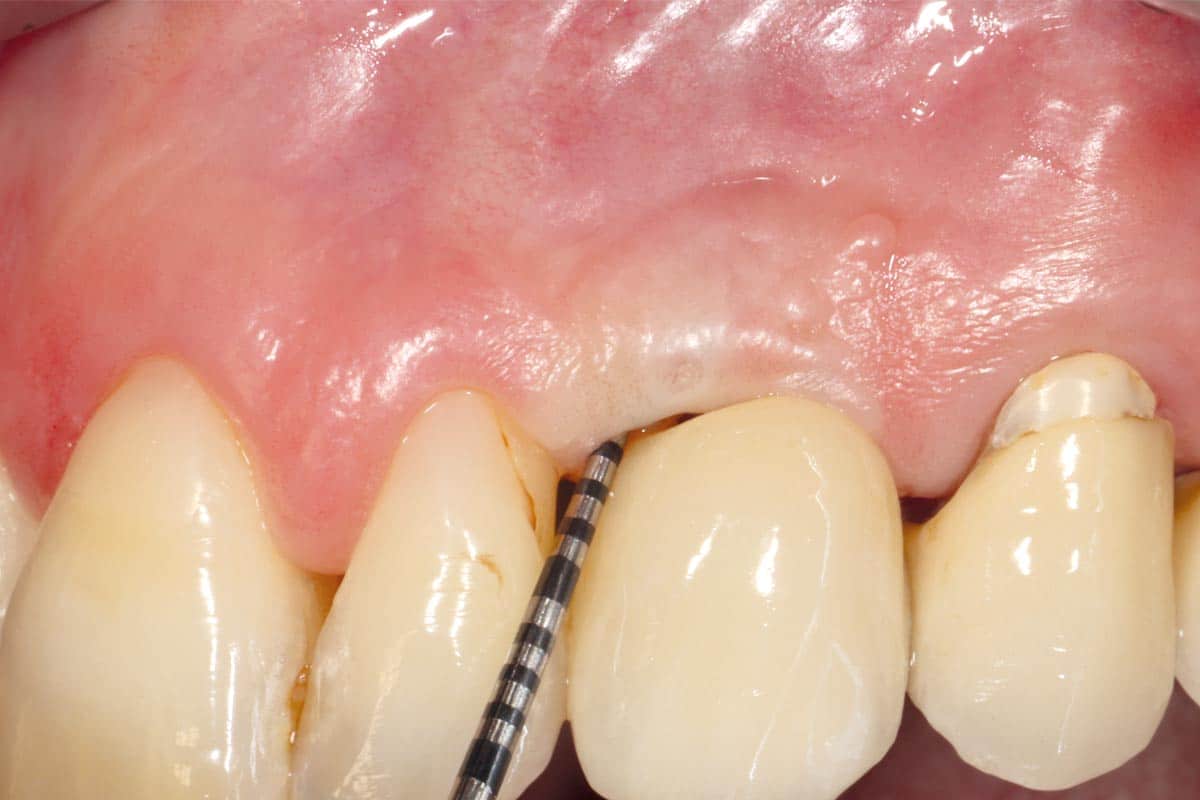

At the 6-month follow-up, clinical and radiographic evaluations demonstrated pronounced new bone formation and favourable soft tissue integration, indicating successful regenerative outcomes. By the 12-month follow-up, bone regeneration had advanced even further, and implant stability was significantly strengthened, confirming the procedure’s lasting success. A CBCT scan at 6 months revealed promising results, which were even more striking at the 12-month mark, demonstrating optimal bone integration and implant stability.